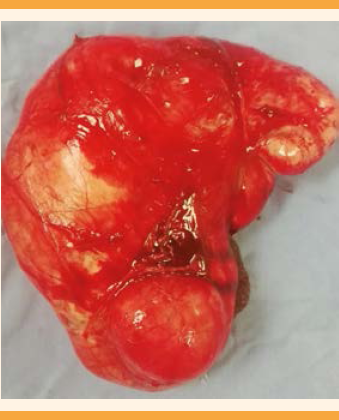

Con el diagnóstico de tumor pélvico y probable miomatosis uterina de grandes elementos, se decidió la laparotomía con estudio transoperatorio que reportó: tumoración de 25 cm, dependiente del ligamento ancho izquierdo y extensión hasta el retroperitoneo, de consistencia sólido-quística; útero de 5 x 6 cm, salpinge izquierda de 11 cm adherida a la tumoración; ovario izquierdo de 3 x 2 cm, blanco-nacarado. La salpinge derecha de 11 cm; ovario derecho de 3 x 2 cm, blanco-nacarado. El sangrado estimado fue de 450 cc; no se informaron complicaciones adicionales. El estudio transoperatorio reportó: leiomioma benigno. Figuras 4, 5 y 6

La paciente evolucionó favorablemente y se dio de alta al segundo día de la operación. Continuó en seguimiento en el servicio de Consulta Externa. El reporte histopatológico fue: tejido de forma y superficie irregular, de 900 g, color marrón-rojizo-opaco, de consistencia semifirme, áreas blanco-grisáceas, de aspecto “arremolinado”, alternando con aéreas rosadas fibrosas. El diagnóstico: leiomioma uterino de patrón histológico convencional. El diagnóstico citológico: líquido peritoneal negativo a elementos neoplásicos malignos, escasas células mesoteliales reactivas y linfocitos aislados. Durante el seguimiento reaccionó satisfactoriamente, por lo que se dio de alta del hospital, con buen pronóstico y adecuada función reproductiva.